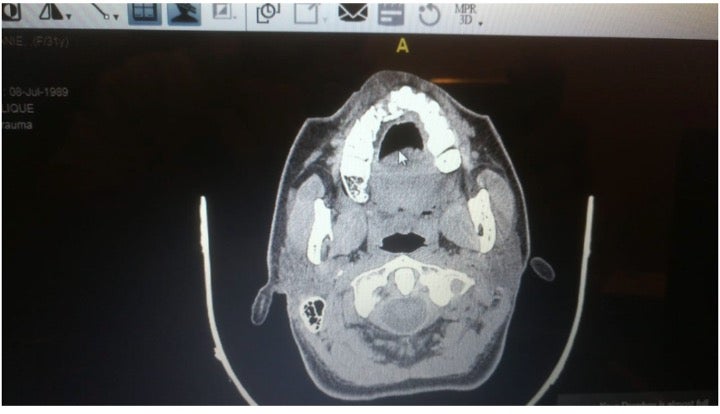

X-ray showing a fracture to a protesters’ maxillary bone after she was shot with a rubber ball.

X-ray showing a fracture to a protesters’ maxillary bone after she was shot with a rubber ball.